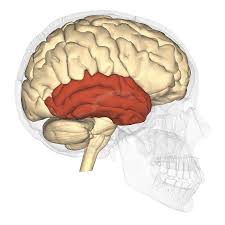

El lóbulo temporal controla la memoria visual, auditiva y comprensión del habla.

Incluye áreas que ayuden a controlar capacidades de habla y escucha, comportamiento y lenguaje.

El área de Wernicke es una porción del lóbulo temporal que se encuentra alrededor del cortex auditivo y formula y entiende el habla.